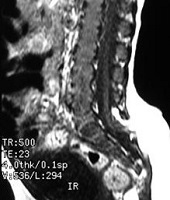

La espina bífida abierta prácticamente ya no se ve, y son el mielomeningocele, el meningocele y el mielocele. El tratamiento preventivo antes del embarazo (3 meses) y durante el embarazo (3 primeros meses) ha hecho que desaparezcan: de cualquier forma cuando ocurre, en nuestra opinión el tratamiento es la intervención quirúrgica.

La espina bífida oculta está formada por las malformaciones como los lipomas, senos dérmicos, diastematomielia, etc. que anclan la médula. Se operan con técnicas microquirúrgicas antes del año de vida.